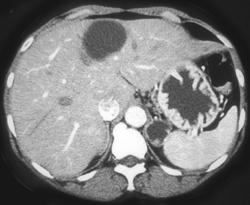

Normal Gastric Folds